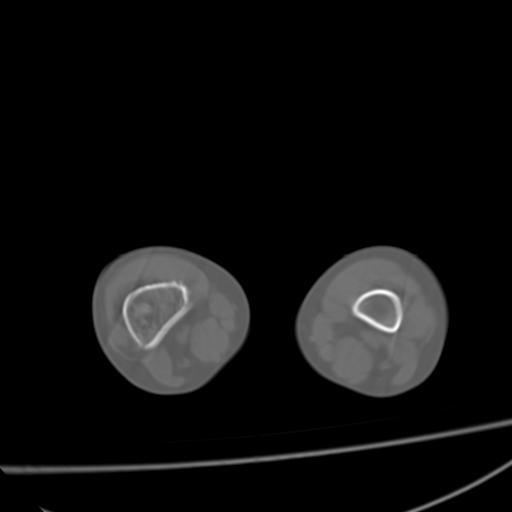

标题: PED0940:M12Y,左股骨下端酸痛畸形 [打印本页]

标题: PED0940:M12Y,左股骨下端酸痛畸形

12岁男孩,左膝关节肿痛8年,近月明显

内生骨软骨瘤?

血友性关节病?